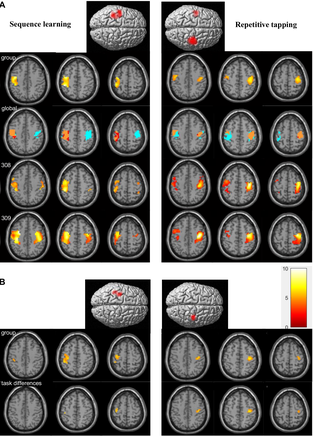

/torins-website-4/images/image-sa193.png)

fMRI study investigating mechanisms of motor control and learning (data analyst)